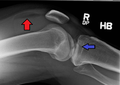

Lipohemarthrosis (presence of fat and blood from bone marrow in the joint space after an intraarticular fracture) seen on X-ray in a person with a subtle tibial plateau fracture

Lipohemarthrosis due to a tibial plateau fracture

Lipohemarthrosis due to a tibial plateau fracture- A tibial plateau fracture seen on X-ray